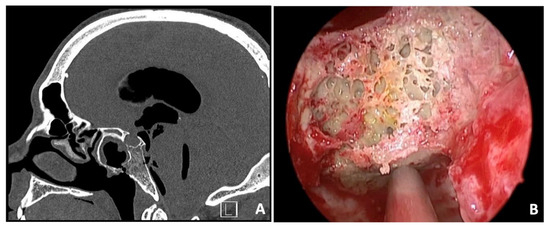

3.6. Case 6—Cholesterol Granuloma

| # 6 | 46 | M | Headache, photophobia | EEA | Resection | Cholesterol granuloma | None | None | 20 months | Alive without disease |